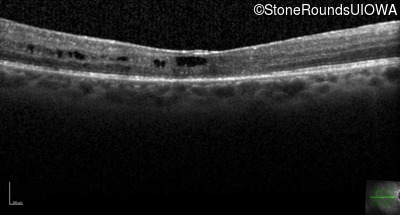

This 43 year old woman first experienced a slight loss of visual acuity at age 23. Fluorescein angiography at that time revealed some vascular leakage from the optic discs and peripheral retina. The maximum combined response of the ERG revealed a selective loss of the b-wave.

Age at visit: 43 years (Visit 2)